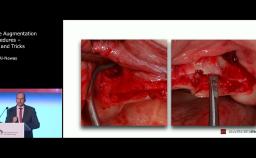

ITI World Symposium 2024 lecture by Waldemar Polido - part of the "GBR/Bone Augmentation" session.

Several surgical techniques can be employed to vertically reconstruct atrophic alveolar bone.However, these ancillary techniques have higher morbidity and are technique sensitive, potentially leading to more complications in the hands of less experienced surgeons. The use of short implants is an alternative to adequately restore partially edentulous patients. Its use has grown exponentially on the last years due to great improvements on imaging, virtual planning, materials and techniques. Recently, ultra-short implants have been introduced, showing promising results for the rehabilitation of patients with severely resorbed alveolar ridges.